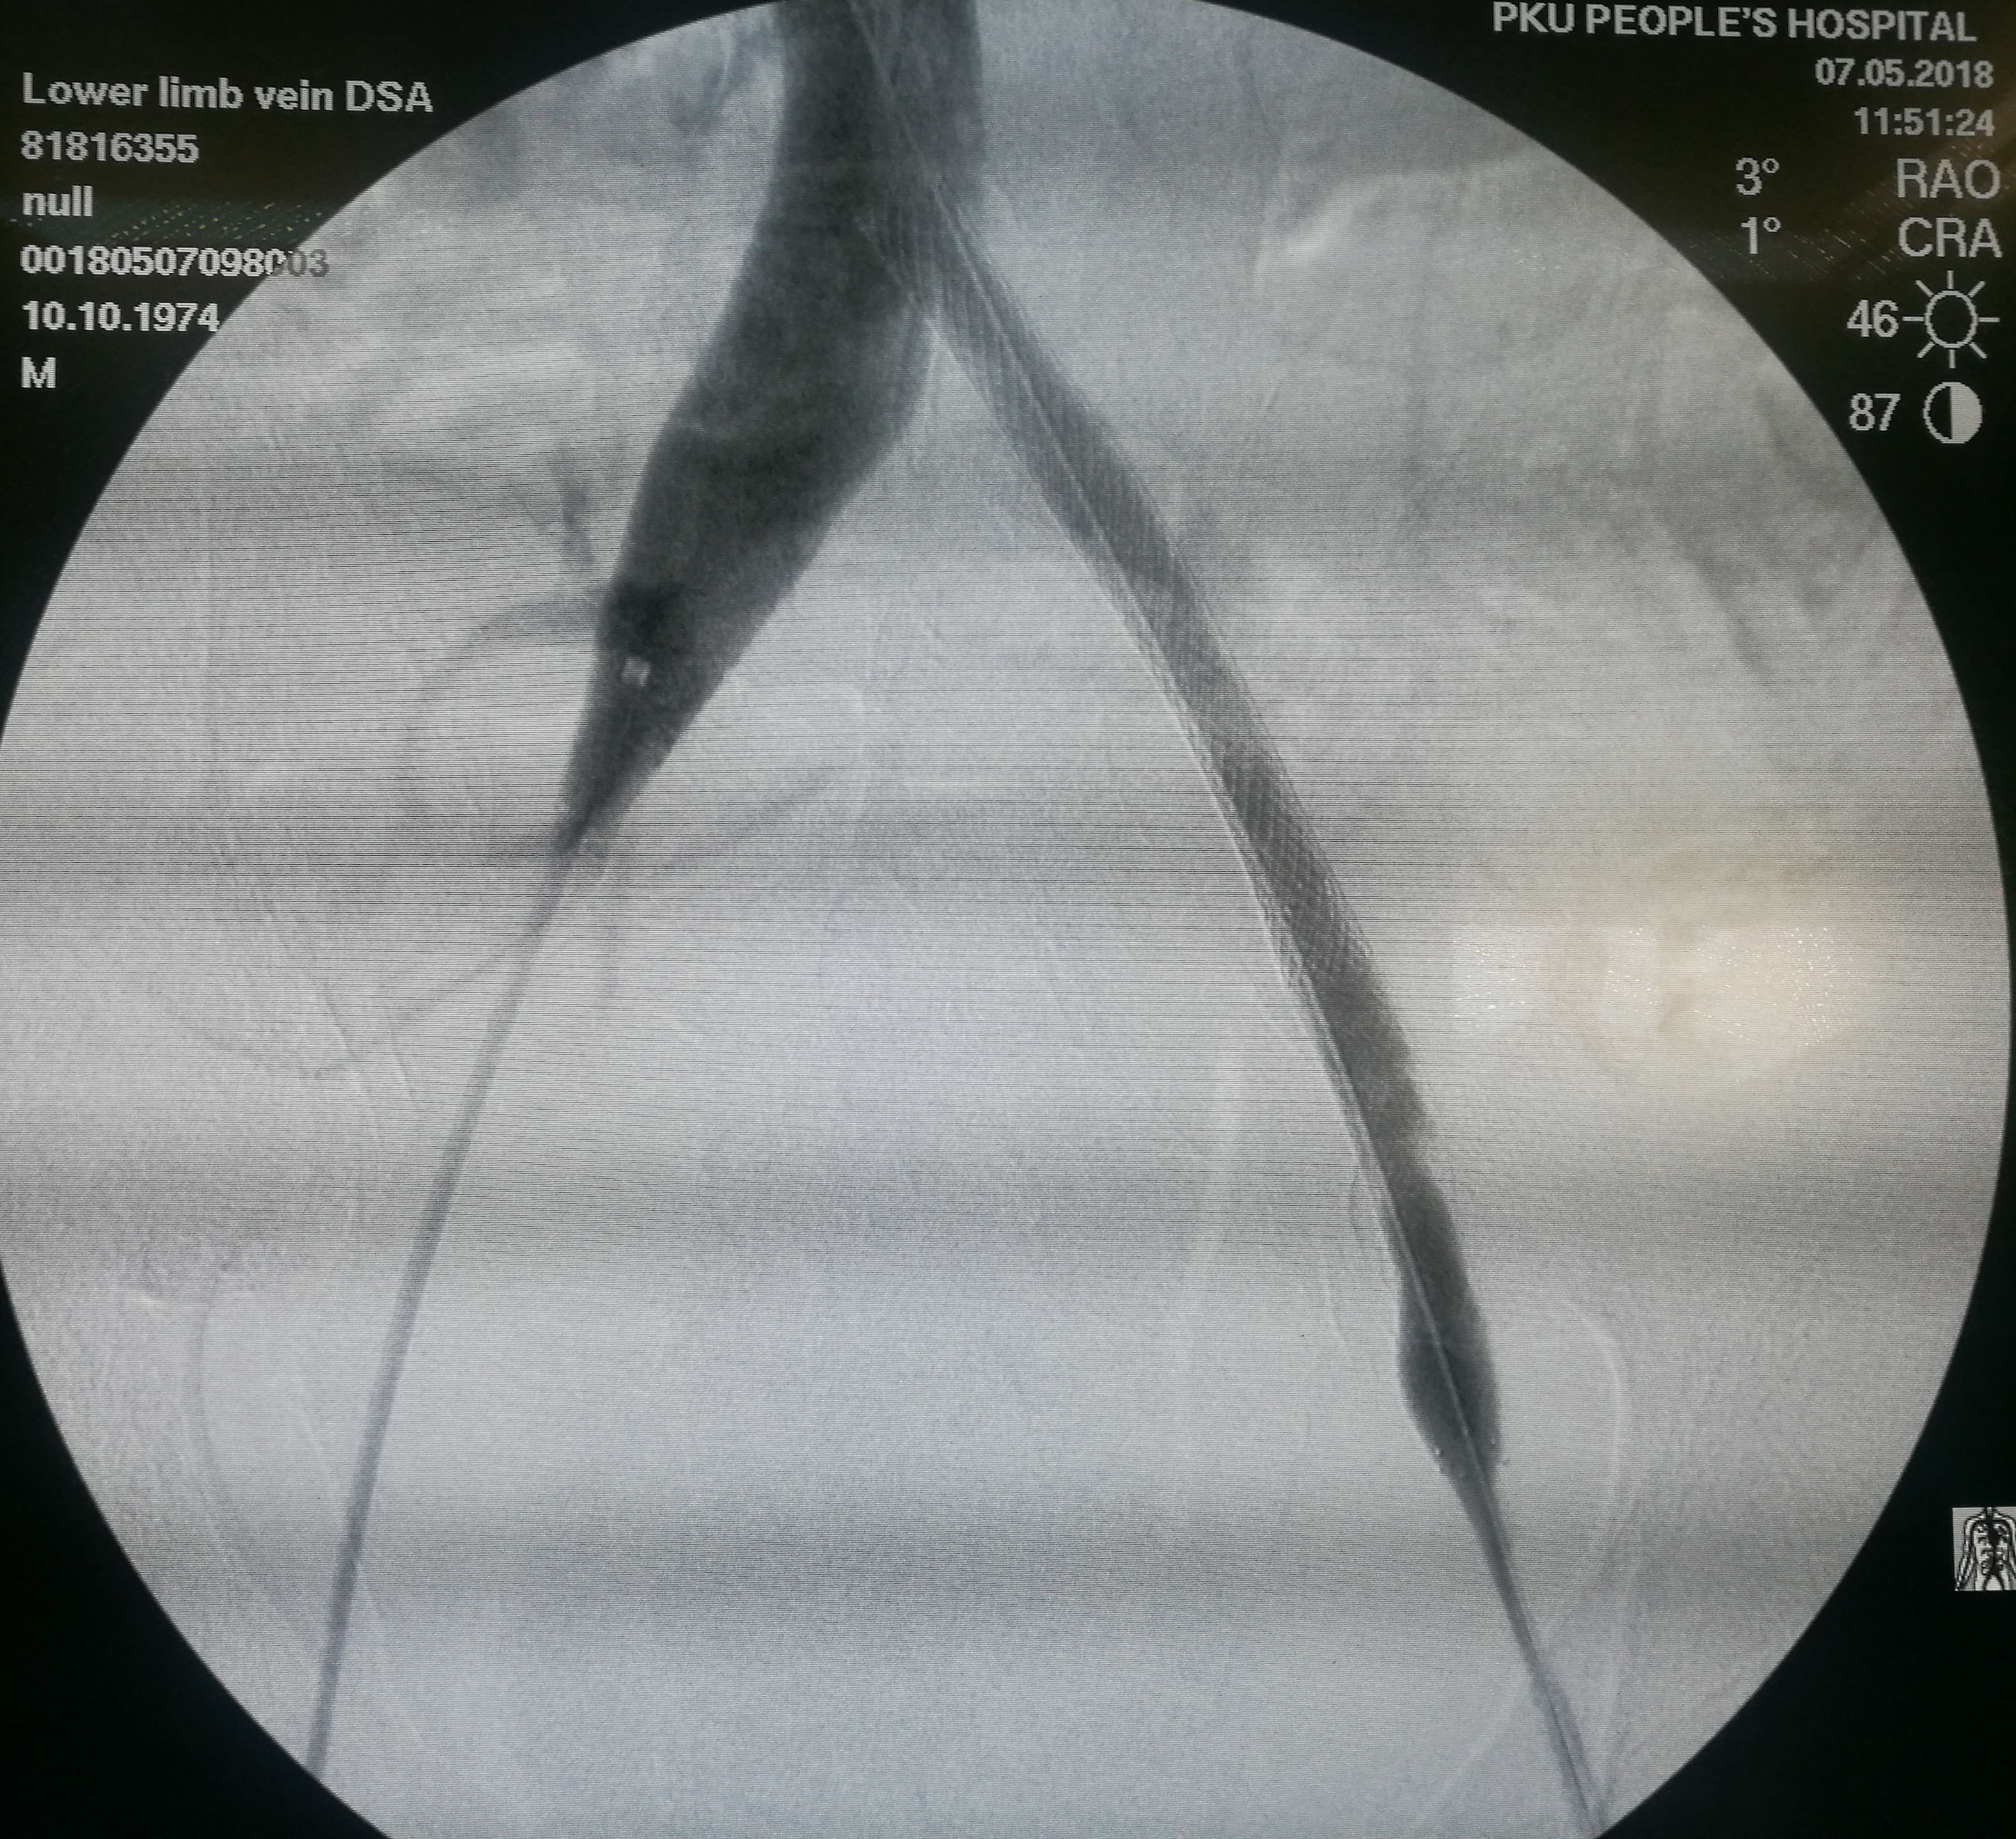

第三个患者是昨天做的,也是反复左下肢深静脉血栓,最近又发作。本次在超声引导下使用肝穿针穿刺左股静脉(其内充满血栓,盲穿无回血),配合超滑导丝,艰难前行约7-8cm后送入血管鞘,之后用导管导丝配合,进入到中线右侧,但从导丝头端的活动度看,未能回到下腔静脉。穿刺右侧股静脉,用SIM1导管从下腔静脉内逆行钩选左侧髂总静脉,在髂总远侧实现和左侧导管的对接,建立真腔轨道。之后在下腔静脉内植入滤器,再对左侧髂总、髂外静脉进行扩张,植入支架。

左髂静脉血栓闭塞

左侧导丝不能回到下腔静脉管腔内

在下腔静脉内留置滤器

植入的支架